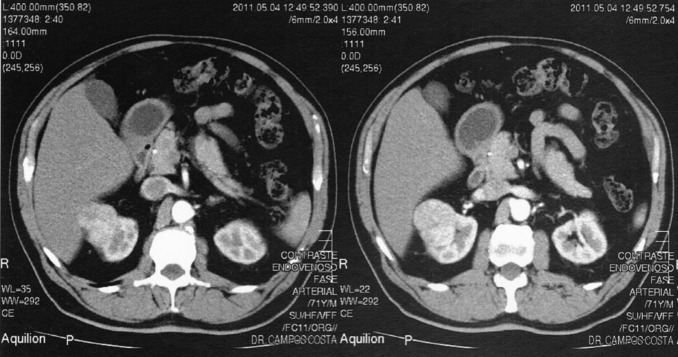

Na consulta de seguimento encontrava‐se assintomático e o exame físico era normal. O estudo analítico trazido pelo doente apresentava as seguintes alterações: glicose 134 mg/dL, HbA1c 6,9%, colesterol total 204 mg/dL, colesterol HDL 34 mg/dL, colesterol LDL 123,6 mg/dL, triglicerídeos 232 mg/dL e creatinina plasmática 1,4 mg/dL (taxa de filtração glomerular estimada [TFGe] – Modification of Diet in Renal Disease [MDRD] – 53,10 mL/min/1,73 m2 ). O exame sumário da urina era normal. Perante o aumento da creatinina plasmática relativamente ao último estudo analítico realizado 6 meses antes (1,25 mg/dL; TFGe – MDRD – 60,69 mL/min/1,73 m2 ), foi solicitada uma ecografia renal que revelou uma formação nodular sólida, de contornos regulares, parcialmente exofítica, na vertente anterior da metade superior do rim direito, com 4,4 × 4,3 cm de diâmetro, sugestiva de neoformação primitiva. O restante exame era normal. Foi realizado estudo complementar com tomografia axial computorizada com contraste ( Figura 1  ;  Figura 2 ), confirmando‐se uma lesão nodular sólida no polo renal superior direito, captante de contraste, com 4,7 × 3,7 × 3,2 cm de diâmetro, com contacto posterior com o lobo hepático direito, compatível com neoplasia de células renais. Perante este diagnóstico, o doente foi referenciado para uma consulta urgente de urologia, tendo sido submetido a nefrectomia radical laparoscópica em junho de 2011. O exame macroscópico da peça cirúrgica revelou uma neoplasia de 4,0 × 4,0 × 4,2 cm de diâmetro, bem delimitada, não capsulada e de localização cortical. No exame histológico, observou‐se uma neoplasia epitelial bem delimitada, revestida por fina cápsula fibrosa, e constituída por toalhas de células de citoplasma amplo, granular e eosinófilo, com núcleos redondos e regulares, com ligeira atipia. O índice mitótico era baixo e não se observou necrose, permeação venosa, linfática ou perineural, nem invasão da cápsula renal. Estes resultados foram diagnósticos de oncocitoma renal.

Resultados da tomografia axial computorizada abdominal com contraste (cortes ...

Figura 2.

Resultados da tomografia axial computorizada abdominal com contraste (cortes transversais) – neoformação no polo renal superior direito.